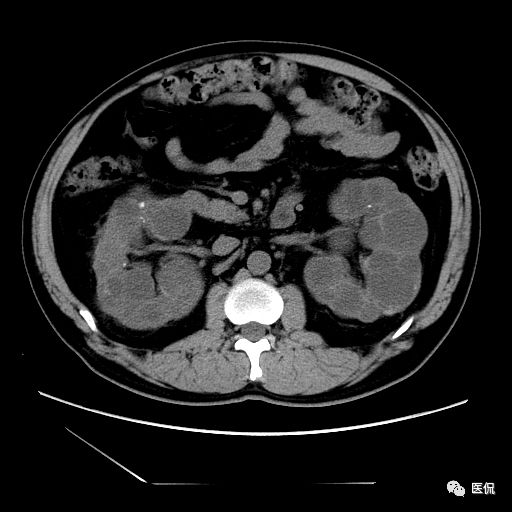

双肾实质可见多发囊性密度灶,其内密度不均匀,并可见钙化灶,增强扫描未见明显强化灶。肾周脂肪间隙清晰,与邻近组织分界清楚。

多囊肾的 CT 表现主要表现为双肾增大,轮廓光滑或有分叶,肾实质内多个大小不等的囊肿呈蜂窝状,多呈水样低密度,增强扫描囊肿本身无强化,而囊肿间正常肾组织增强,对比明显。当囊肿张力过高,使囊壁上毛细血管牵拉破裂出血时,表现为囊肿内稍高密度影,随访CT 值减低。囊壁钙化,表现为点线状高密度影像,随访CT值无变化。有文献报道约 30%病例可并发多囊肝或多囊胰。